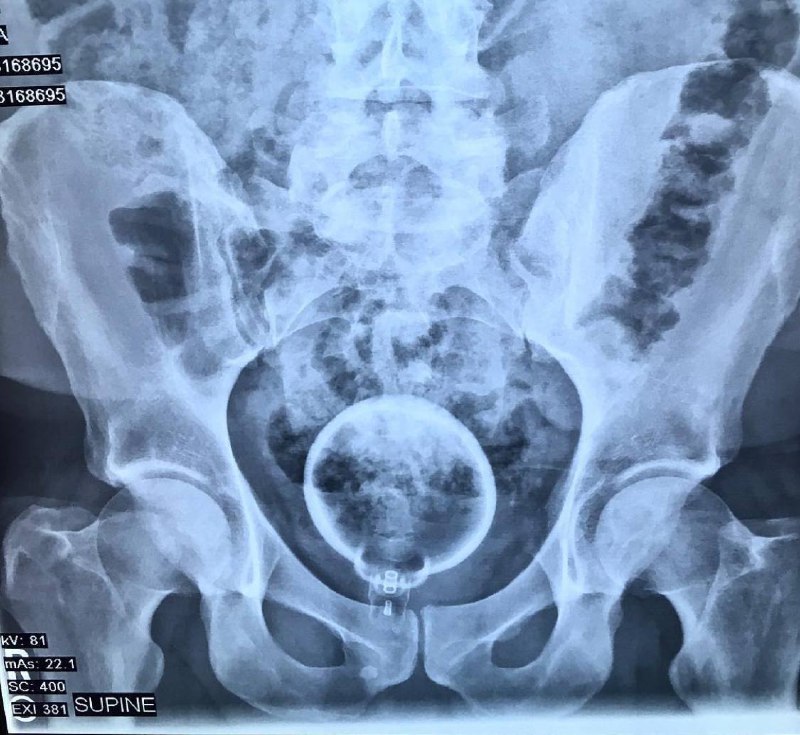

Самые странные предметы, которые проявлял рентген в людях 😨

11 мар. 2026 г.

4.4k 61 28

Посмотрите на этот полный боли снимок. Этот пациент уже не придумывал истории про то, как случайно упал на флакон духов. Ему было настолько больно, что он не мог говорить. Дело в том, что крышка о

4 мар. 2026 г.

4.2k 96 33